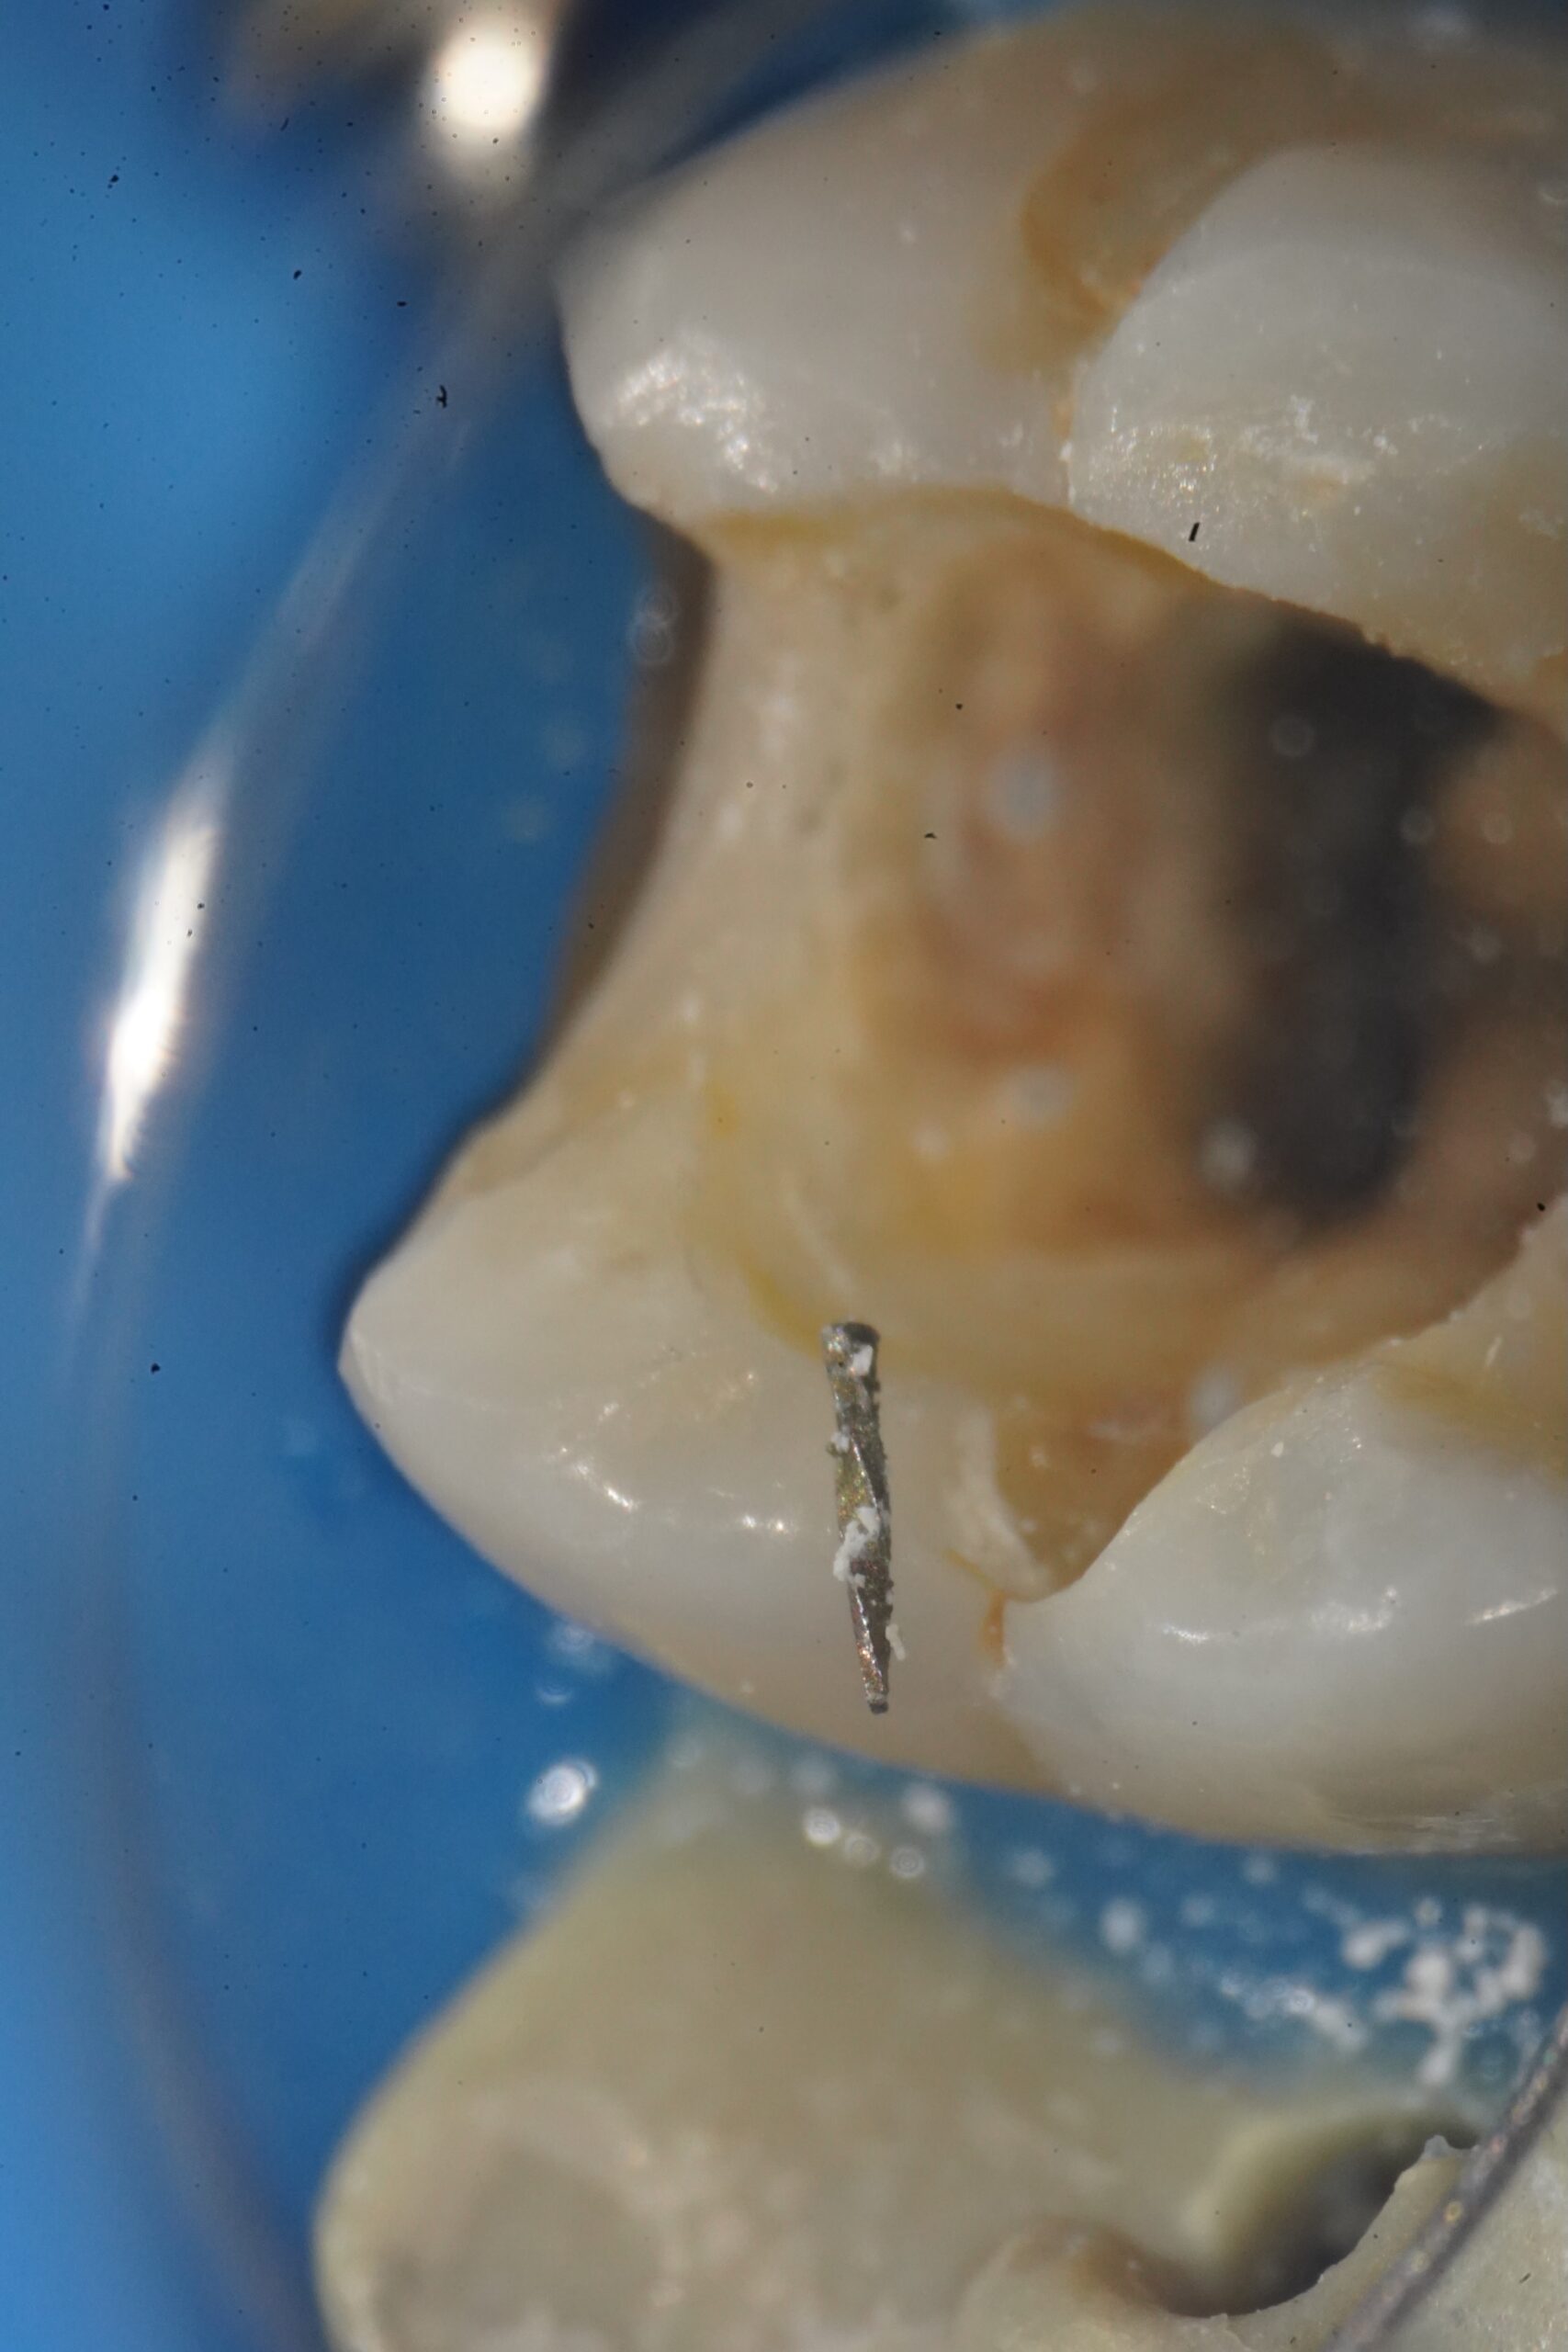

最小限の侵襲で、粘膜の挫滅や出血が抑えられるように抜歯

根尖が複雑に湾曲しており、骨を掴んでいた